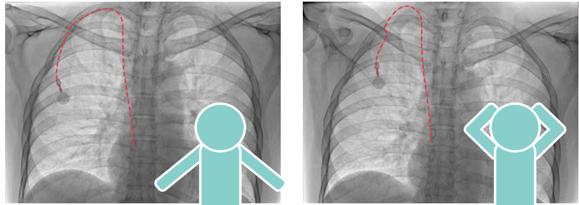

3.上肢を挙上させ血管とカテーテルをまっすぐにする

2.日常の活動や運動。立位や上司の挙上により、内頚静脈や他の静脈への移動も起こりうる。カテーテル交換をおこなったり、別の部位への造設も検討する